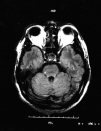

Fig. 1. Resonancia magnética cerebral en la que se observan pequeños infartos en tálamo y protuberancia derecha.